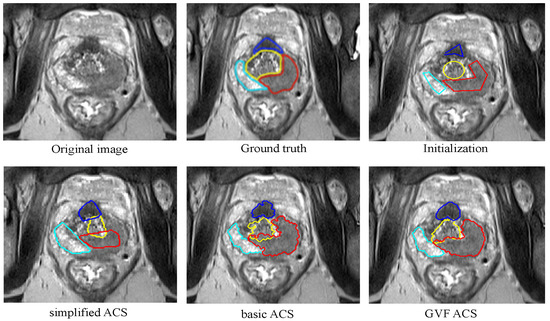

In this section, we present a deep analysis of the results of a single segmentation experiment performed using the implemented algorithms, namely the Basic ACS, Simplified ACS and GVF ACS versions of the snake-based models. For all the cases, the initial contours used for all the zones are shown in Figure 11.

The results for all the algorithms and the ground truth for the selected image are shown in the Figure 12.

From this experiment, it is possible to confirm what it has been said in previous sections. The Basic ACS algorithm performs relatively well when there is some gradient information between different areas. In this image, the cyan and the blue contours (corresponding to the PZ and CZ, respectively) are practically attached to the borders; the contour corresponding to the TZ (yellow contour) is almost perfect. Nonetheless, the tumour area invades the TZ area, since the intensities contrast between them is not enough in order to define a good edge.

For the case of Simplified ACS, the results are not so satisfactory. This algorithm is uses simplifications of the formulas described in [12]. It has been tested for heart’s left ventricle segmentation and it has a good performance in both, quality and speed, but for prostate segmentation, this is not true. Except for the TZ, all the results take part of the other zones, and only when the edge is too strong, the snake seems to be perfectly attached to it.

Finally, as it is expected, the Gradient Vector Flow implementation overcomes all the problems, and the curves are strongly attached to the borders of each zone. There is only a little overlapping between the tumour and the TZ.

Another point to observe is the smoothness of the results from Basic ACS and GVF ACS. None of them include either a shape prior or the smoothing factor. This allows the snake to evolve in any shape, which is desired in this case, since there is not a single prior that work for all the prostate zones. Additionally, for the same reason, a generic post-processing that increases the smoothness of the curves is not trivial to implement. This problem is visible mainly in the result given by the Basic ACS, where all the contours do not present smooth borders. Nonetheless, the GVF ACS generates a result that even without these factors, the outcomes are not so jagged. Once again, the addition of the Gradient Vector Flow component surpasses the results given by the Basic ACS.

Figure 12. Segmentation results and ground truth for all the algorithms implemented.